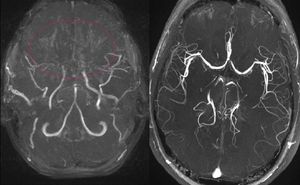

모야모야병은 뇌혈관 조영술로 진단하는 것이 원칙이지만, 자기 공명 영상(MRI) 및 자기 공명 혈관 조영술(MRA)로도 진단 기준을 충족하면 반드시 뇌혈관 조영술을 할 필요는 없다. 다만, 병의 초기 단계에서는 MRA로 확인이 어려울 수 있으므로 주의해야 한다.[26] 단일 광자 방출 전산화 단층 촬영(SPECT), 양전자 방출 단층 촬영(PET), 뇌파 검사 등도 진단에 사용될 수 있다.

자기 공명 혈관 조영술(MRA) 역시 스즈키의 등급 분류 시스템과 좋은 상관관계를 보이며, 모야모야병을 진단하는 데 유용하다.[14]

MRI T1 강조 영상에서는 양쪽 기저핵 부근에 이상 혈관망을 반영하여 점상의 저흡수 영역이 확인된다.[26] MRA에서는 혈관 조영과 유사한 소견을 보인다. 모야모야병의 진단에는 MRA가 유용하며, 스즈키 등급 분류 시스템과 좋은 상관관계를 보인다.[14]원칙적으로는 뇌혈관 조영술로 진단하지만, MRI 및 MRA로 진단 기준을 충족하면 반드시 뇌혈관 조영술을 할 필요는 없다. 다만 병기가 초기인 경우에는 MRA로 확인이 어려운 경우가 많으므로 주의해야 한다. 1.5T 이상의 정자장 강도의 기종을 사용한 TOF법으로 MRA에서 두개 내 내경동맥 종말부에 협착 또는 폐색이 관찰되거나, MRA에서 대뇌 기저핵부에 이상 혈관망이 관찰되는 경우에는 확진된다.[26]